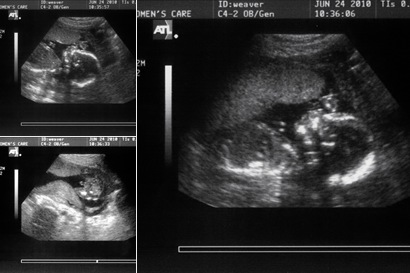

One week ago this post; a very amazing thing happen to me and my family. God blessed Sarah and I with a hansom ten finger and toes little boy. He weighed 8lbs 12oz, is 22

inches long and has a set of longs that any opera singer would cherish. Reagan R. Trump, my little me, has been so great to have around and has made Macey just a little jealous when he is in my arms. Monday the 15th was an adventuress day; our day started around 5:30am and ended just before midnight. Sarah and I really just hung out all day and she didn’t really have many contractions at all, but around eleven the contractions really picked up and things got really exciting. Sarah’s mom and my mom not only got to be in the room for Reagan’s birth they got to hold Sarah’s legs up for her; my sister got to record the entire birthing process (the video needs to be hacked and recoded, the camera didn’t close the file properly) I also got to be a part of the festivities, Sarah got to push and I got to catch our new little baby. That’s right; I got to catch my new little buddy. I really got to catch him, the only thing the doctor did was coach me on what to do and make sure the cord didn’t get wrapped around his neck. Wow it was so flipping cool and it is still so fresh in my head I love it. Once he popped out I set him on Sarah’s chest and gazed in amazement on what had just happen. Next thing I knew I was grabbing scissors and cutting the cord physically linking my son to my wife. That cord is some tough stuff to cut threw and just a little scary, after he was all cleaned up I got to cut the cord closer to his belly. Reagan was a little screamer while getting all cleaned up and I was all smiles, (not because he was screaming, but because I was so happy). After he was born and the video was shut off we really stared taking pictures, three camera were just flashing away for about an hour. Sarah looked so happy and relieved, I was so excited and all smiles, my mom was crying and my sister was amazed at how “not so gross or bad” the whole process was, and Sarah’s mom looked so proud she had a little grandson. Rich came up too but had to wait out in the hallway because Sarah didn’t want any guys seeing the personals; that weren’t so personal at the time. All in all it was a wonderfully great night and has really changed my life for the better even if I lose a little sleep each night.